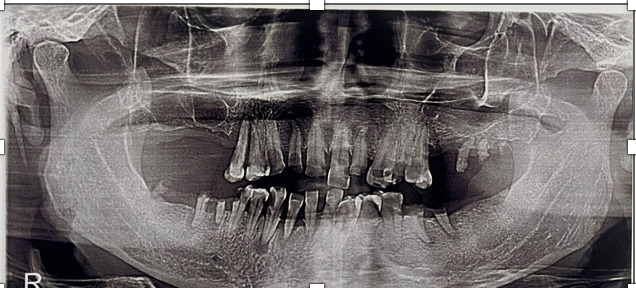

Periodontitis is one of the most common periodontal diseases affecting both elderly individuals and heavy smokers. This case report aims to describe the management of a geriatric patient with generalized chronic periodontitis and a history of heavy smoking. A 63-year-old male patient presented with a chief complaint of mobile teeth that had persisted for the past three months. Intraoral examination revealed necrosis, cervical caries, gingival recession, and poor oral hygiene. The treatment included extraction of the mobile teeth and socket curettage to remove necrotic tissue. The patient was prescribed antibiotics and analgesics, followed by a one-week post-operative evaluation. The patient reported no pain or swelling after extraction, and the healing process was satisfactory, with no signs of infection. The patient was also informed about a long-term treatment plan involving the fabrication of a prosthesis. Tooth extraction in patients with chronic periodontitis requires careful consideration of both clinical and non-clinical factors. This case highlights the importance of a comprehensive approach in the management of periodontitis in elderly heavy smokers.References